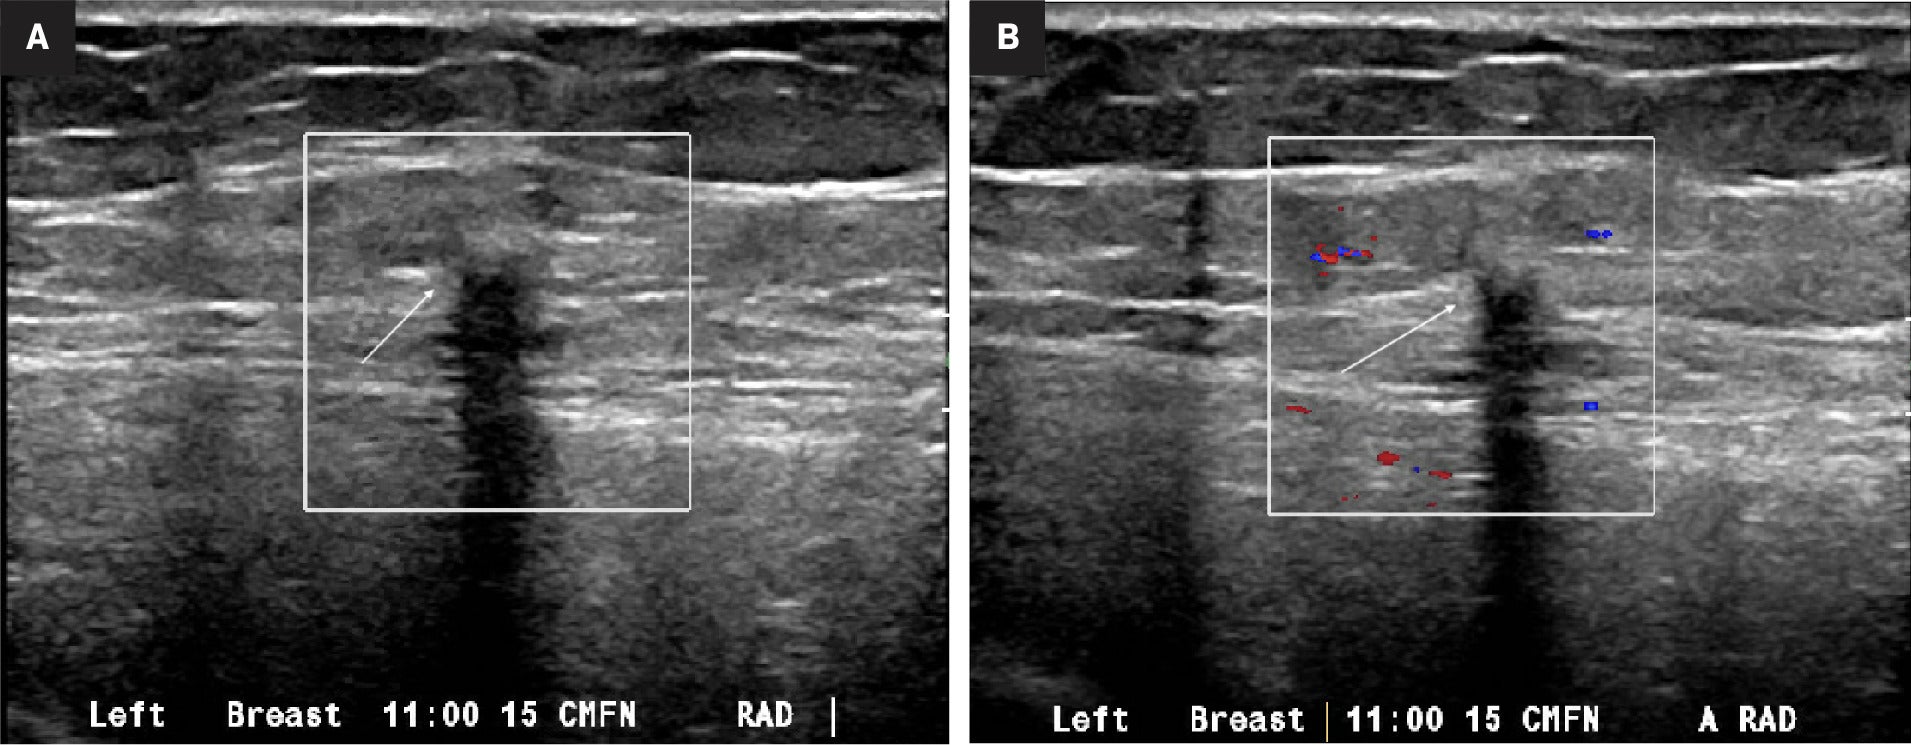

Breast Granular Cell Tumor

By Elmira Taghi-Zadeh, MD; Moumita Saha Roy Choudhury, MD; Mohanad Shaar, MD; Evita Singh, MD